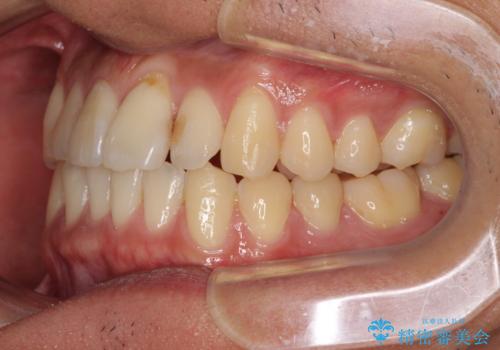

気になる前歯のデコボコをインビザラインで解消

- 前歯のデコボコを気にして来院された患者様です。

主に下顎歯列全体の後方移動とIPR(歯と歯の間を削る)によってデコボコが解消するように設計し、インビザラインにより治療を行うこととしました。

インビザライン矯正特有の、治療後半で前歯のみが強く接触する症状が発現し、咬み合わせ改善に期間を要することとなりました。